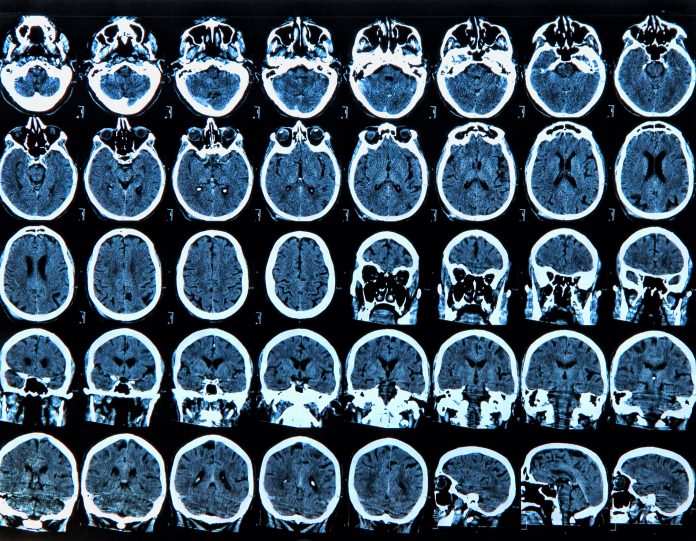

The team are also testing a ‘neurofeedback’ system which measures the user’s brain activity in real-time with an EEG cap, teaching him or her to increase activity in relevant brain regions.

Neurofeedback aims to gain control over brain activity in brain regions associated with increased pain resilience, enabling patients to manage their own chronic pain better.

The user’s increased pain resilience levels will be tested by asking them to submerge their hand in cold water, known as the Cold Pressor Test.